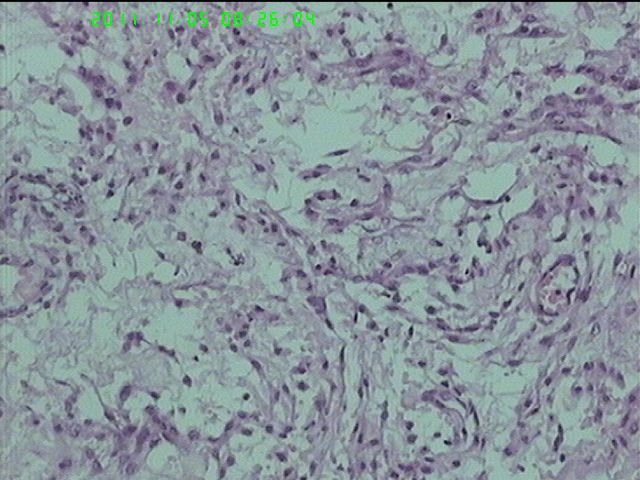

37岁女性患者,左卵巢肿块术中快速:恶性。术后左卵巢囊实性肿块14*9*5CM,灰黄色,部分乳头状,粘液样外观;子宫内膜厚1.5CM;网膜见多个小结节。图1--14左卵巢  15-19网膜  20--23宫腔

在图中有明确浸润吗?好像看不出来,但是网膜显示非侵袭性。宫腔图片没有显示浸润。请多上边缘处图像。

请临床查有无阑尾病变,排除阑尾肿瘤转移后,如果没有明确浸润,倾向粘液性*交界性肿瘤伴腹膜种植,肠型。

总之先排除阑尾来源,再看有无浸润,有浸润才打癌。

卵巢粘液性囊腺癌伴内膜及网膜转移。

图1、4、5、6、11中可见疏松组织,网状结构,并见可疑透明小体,加上患者年纪较年轻,卵黄囊瘤不能除外,粘液腺结构可能是卵黄囊中的内胚层成分。且形态上与网膜结节相似。